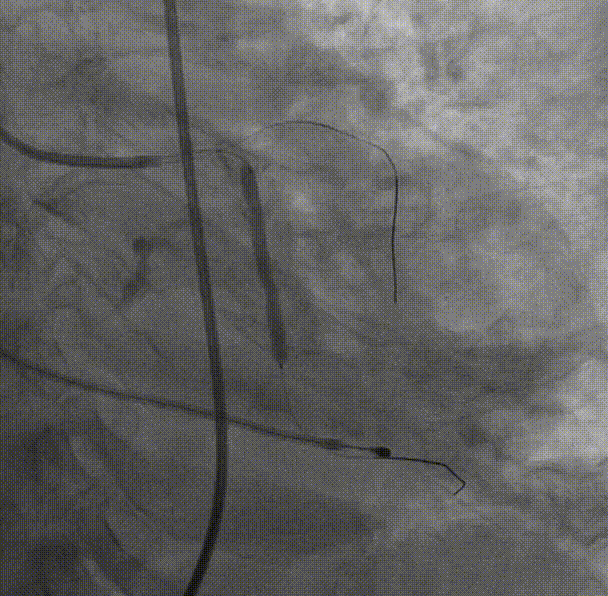

TAVR手术

主动脉根部造影

直头导丝跨瓣

20球囊预扩-无腰征,有少量瓣周漏,故选择L26VenusA-Plus瓣膜。

L26VenusA-Plus输送器过弓 瓣膜定位

瓣膜释放到工作区,造影评估瓣周漏及冠脉情况。

最后造影评估 无瓣周漏瓣膜展开良好,故无需后扩。